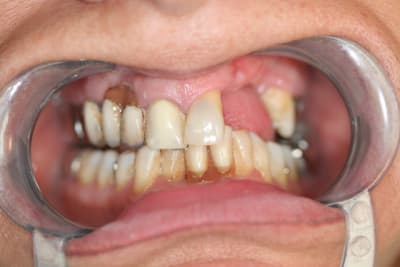

je me permet de ressusciter ce poste car j'ai placé la prothèse il y a un mois.

photo 1: début du cas

photo 2: fin d'intervention

photo 3: j+3mois

photo 4 +5: prise d'empreintes

photo 6-7-8-9: couronne finie.

merci de votre attention :)

PS: le patient ne veux pas faire celle d'à coté.

grr, moi ça me démange...